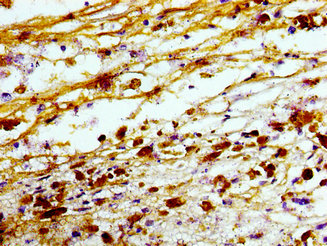

Immunohistochemistry of paraffin-embedded human melanoma using CSB-PA024405LA01HU at dilution of 1:100